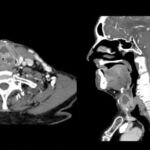

Un examen de tomografía axial computarizada (TAC) cervical es una herramienta de diagnóstico por…

El examen TAC cervical es una herramienta médica importante que ayuda en el diagnóstico…

El TAC cervical, o tomografía axial computarizada cervical, es una técnica de imagen médica…